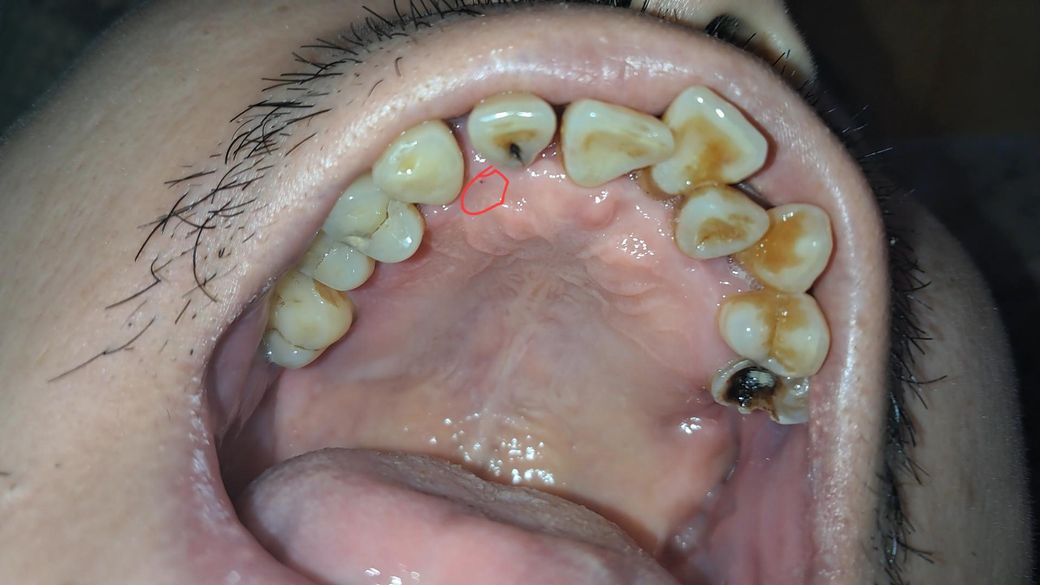

구강암인지 봐주세요 잇몸에 작은 붉은 점 있어요

잇몸을 살피던 중 붉은 점을 발견 했어요

구강암 증상이 아닌지 의심이 들어 이렇게 글을 씁니다

• 1번 째 사진